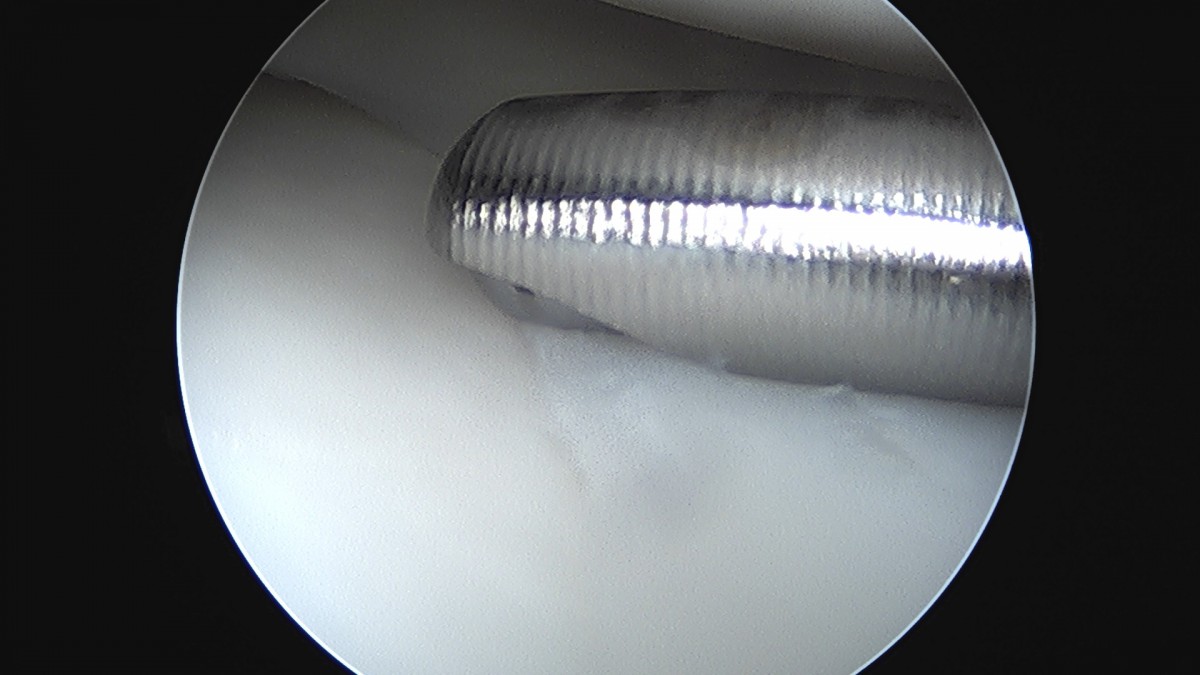

이재상원장님 무릎 반월상 연골판 절제술 김건O 환자

dae765e4d9ac96aee867c9d6292d8784_1758006494_6445.jpg